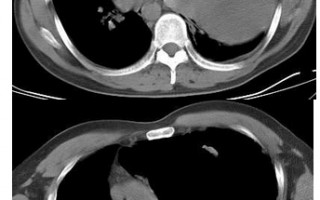

CT减影技术,ct减影处理方法 ⟨技术原理⟩CT减影技术通过数字差分处理消除非管结构干扰,其心流程为:双期扫描:先获取平扫(蒙片),再注射对比剂进行增扫描[[1]... 用户投稿 2025-05-31 100